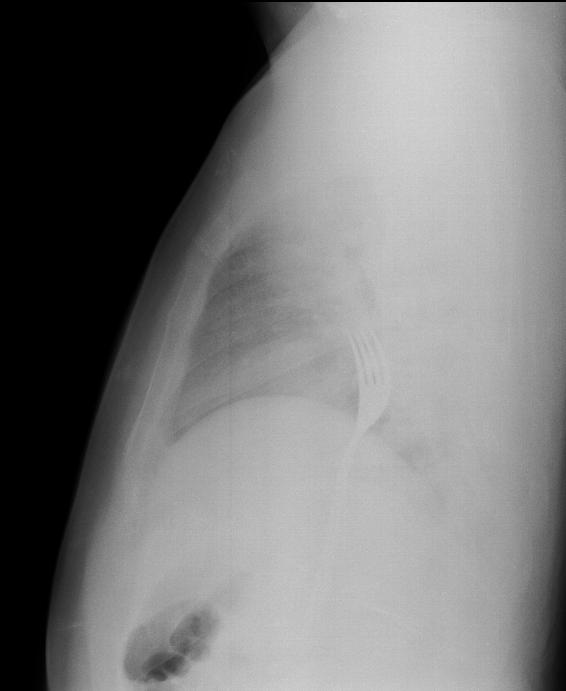

Çekilen röntgen filmlerinde, çatalın midede olduğu görüldü. O.A'nın midesinden 15 santimetrelik metal çatal, başarılı operasyonla çıkarıldı. O.A, taburcu edildi.

Kontrollerde çatalın yemek borusunun sonuna kadar inip midede kaldığını gördüklerini aktaran Erikoğlu, büyük olması nedeniyle çatalı operasyonla mideden küçük kesiyle çıkardıklarını ifade etti.